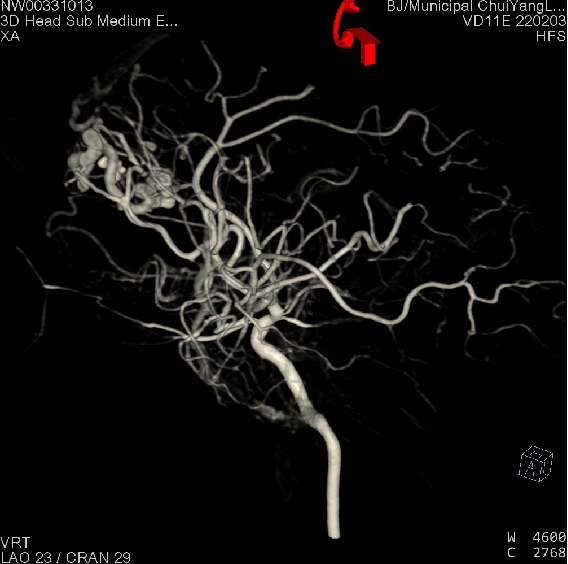

开颅手术于复合手术室进行。麻醉成功后,张锟会同刘耀东和神经外科副主任医师董雪涛,迅速完成开颅。医生们在显微镜下仔细操作,最大限度减少出血,初步快速清除硬膜下血肿及脑内血肿,为介入治疗赢得时间。与此同时,神经外科介入治疗团队副主任医师刘磊、主治医师段练与医师王绍珍迅速完成脑血管造影检查,发现左侧额叶脑血管畸形团,并成功进行了栓塞治疗。术后造影畸形血管团未再显影,随后由董雪涛及刘耀东继续完成血肿清除并去除骨瓣减压,术中出血200ml,最大程度上避免了出现因稀缺血型输血困难的问题。

左侧额叶巨大血管畸形团(术前DSA)

栓塞后左侧额叶血管畸形团消失(术后DSA)